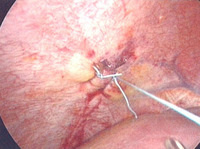

Vista laparoscópica de lesión diafragmática

Colección del MetroHealth Medical Center